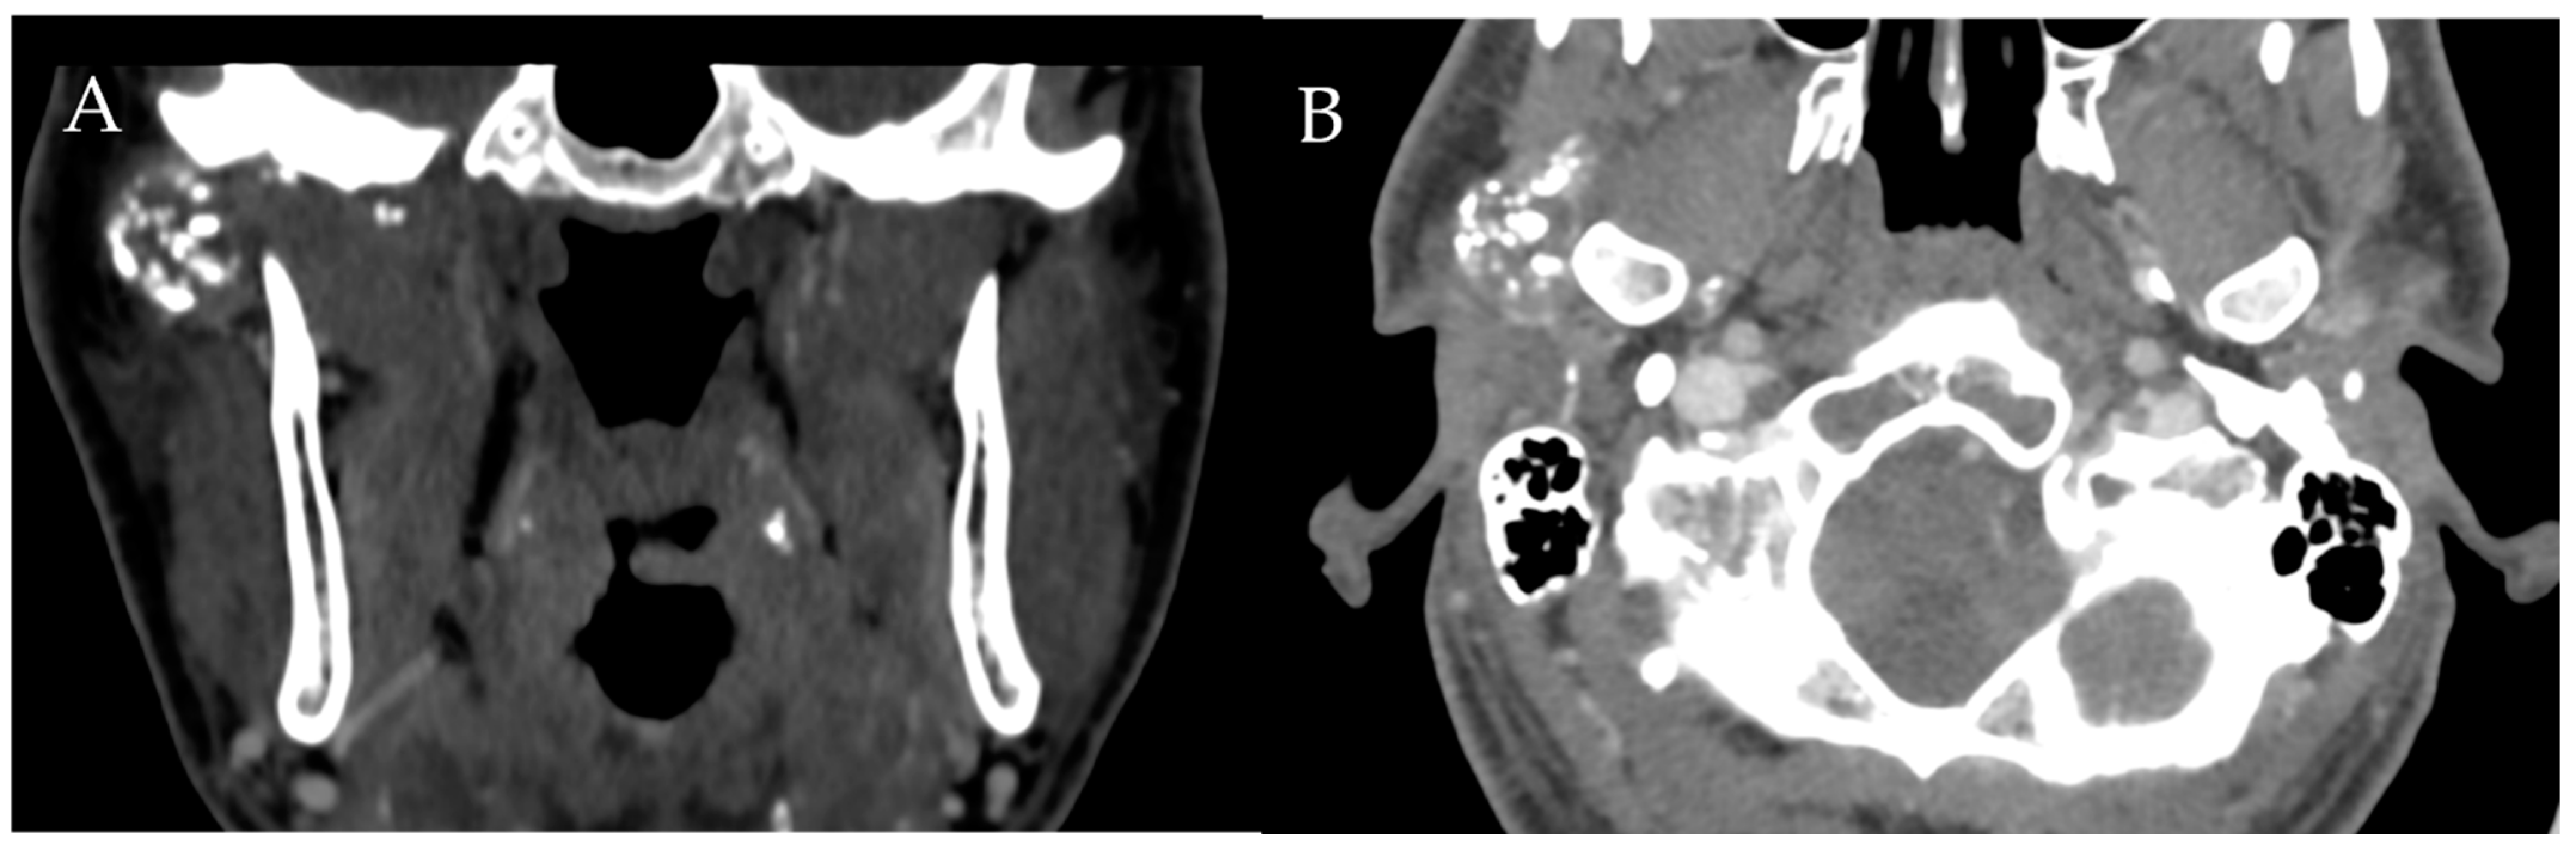

Figure 10. Synovial Chondromatosis. Coronal (A) and axial (B) CT shows multiple calcified loose bodies in the right TMJ consistent with synovial chondromatosis.

Synovial chondromatosis (SC) is a rare, benign synovial proliferative disease characterized by the growth of cartilaginous nodules in the synovium that eventually calcify and detach from the joint. As a result, SC usually presents with joint effusion and multiple loose bodies (Figure 10). Unlike PVNS, which never calcifies, the loose bodies in SC are typically calcified. Therefore, a CT can help differentiate the two entities [3,9].